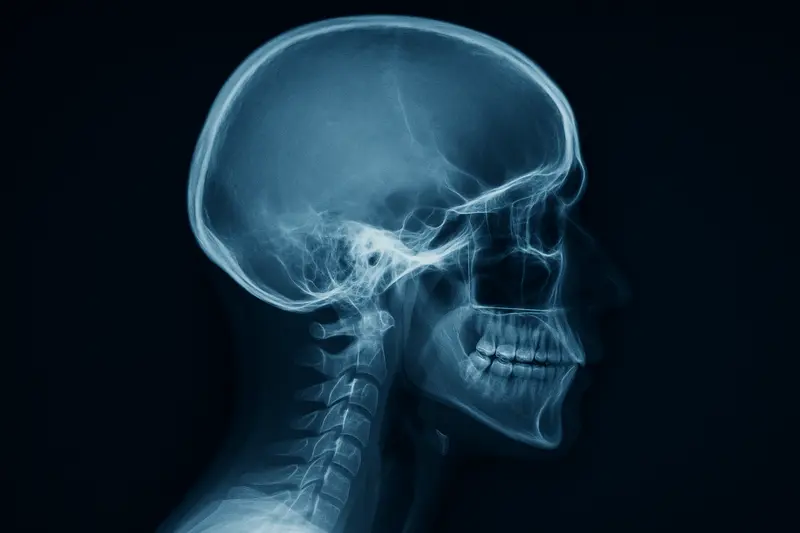

Рентген черепа

Рентген черепа Рентгенография костей черепа, известная как краниография, остается одним из фундаментальных и высокоинформативных методов диагностики в современной медицине. Этот доступный и быстрый метод позволяет визуализировать костные структуры мозгового и лицевого отделов черепа, выступая первым инструментом в оценке их целостности и состояния. Несмотря на появление более сложных технологий, таких как КТ и МРТ, рентгенограмма черепа не утратила своей актуальности благодаря высокой точности в выявлении переломов, трещин и ряда других патологий. Современное цифровое оборудование, используемое в передовых медицинских учреждениях, делает эту процедуру безопасной, минимально лучевой и комфортной для пациентов любого возраста.

Основная цель, с которой назначается краниография черепа, — это детальная оценка состояния костных тканей. Данное исследование позволяет врачу решить ряд критически важных диагностических задач: определить целостность костей черепной коробки после травмы, выявить врожденные или приобретенные аномалии развития, диагностировать воспалительные заболевания костной ткани и обнаружить признаки новообразований. Рентгеновский снимок черепа позволяет оценить состояние придаточных пазух носа, выявить косвенные признаки повышенного внутричерепного давления и патологий гипофиза. Эта диагностика является отправной точкой для постановки точного диагноза и определения дальнейшей тактики лечения.